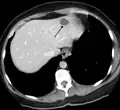

- A liver hemangioma as seen on CT

Infantile hemangiomas in the liver are found in 16% of all liver hemangiomas. Its sizes are usually less than 1 to 2 cm in diameter. It may show a "flash-filling" phenomenon in which there is a fast enhancement of the contrast material in the lesion instead of slow, centripetal, nodular filling of the lesions in usual hemangiomas. On CT and MRI, it shows rapid filling during arterial phase, with contrast retention in venous and delayed phases.[40]